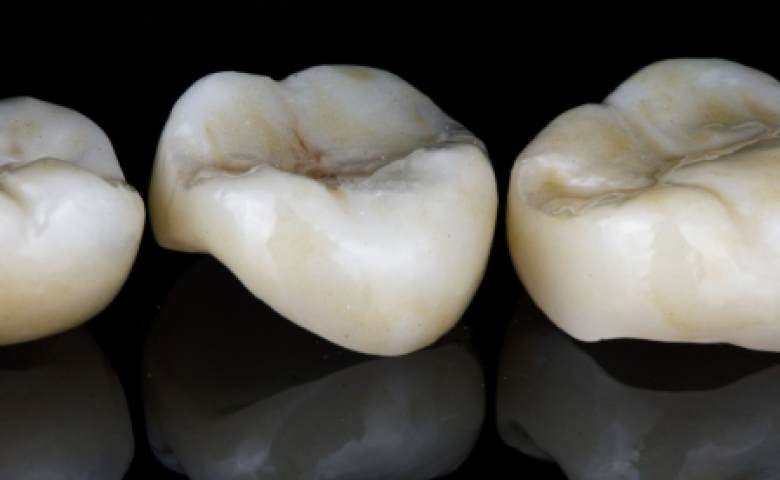

We use advanced dental technology across many areas of the practice, from digital imaging and scanning to treatments for dental implants, Invisalign, hygiene care and cosmetic dentistry. Every piece of equipment we introduce is chosen because it helps us deliver a higher standard of care.